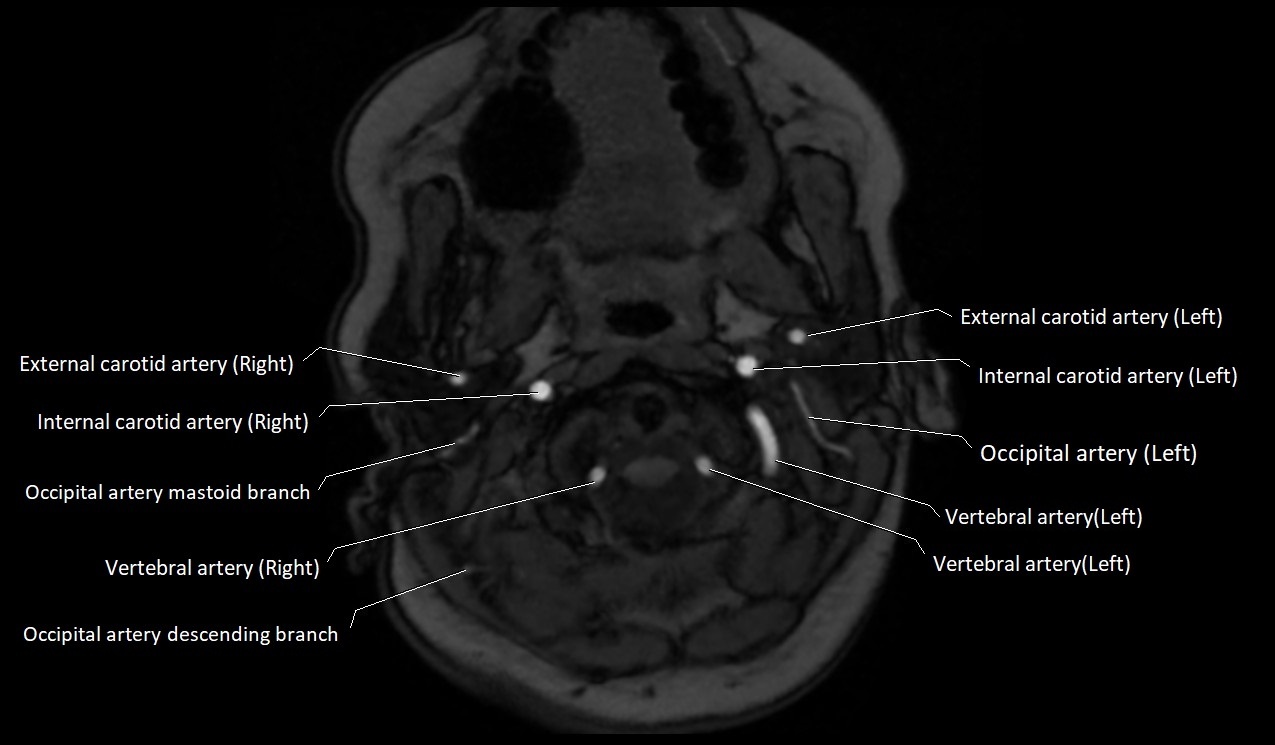

MRI images

image